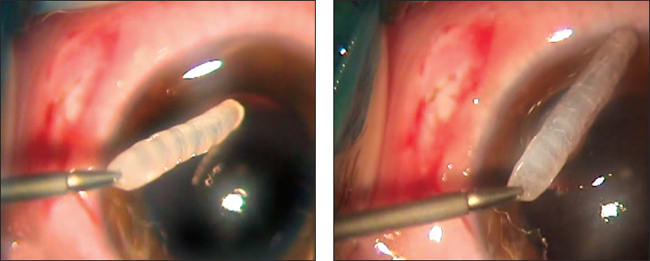

The first step in removing the larva was that it was fixed by the aspiration cannula and tucked up for expansion to a 2-mm sclerotomy (Figure 2). Next, we carefully removed the larva from the vitreous cavity with vitreal forceps, without damaging its integrity (Figure 3), and we placed it in physiological solution for further identification. As the final step, we performed endolaser coagulation around the retinal break and closure of the sclerotomy.

Figure 3. The larva was removed from the vitreous cavity with vitreal forceps.